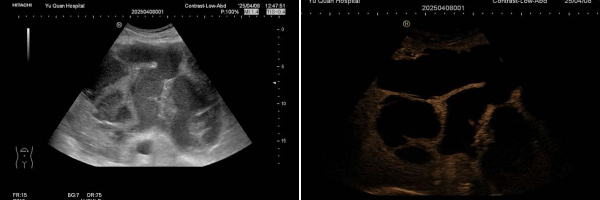

该患者因在外院发现肝脏占位入住我院普外科。入院时腹胀、无腹痛、发热。增强CT和增强MRI均提示肝脏巨大囊实性占位,但无法明确病变性质。入院后完善相关化验检查:白细胞15.76×*10^9/L,中性粒细胞计数13.84×*10^9/L,C反应蛋白128.0mg/L,葡萄糖7.83mmol/L,肿瘤标志物(-),患者有糖尿病病史且血糖控制不佳,且入院后已出现发热症状,考虑肝脓肿可能。普外科请超声医学科会诊:常规超声探查肝左叶可见一囊实性包块,大小约19.9x14.2x15.5cm。即刻行超声造影检查,实时动态观察该病灶的血流灌注方式:病灶内动脉期呈典型的网格样高增强,中央可见无增强区,门脉期及延迟期呈等增强,符合肝脓肿的超声造影表现。